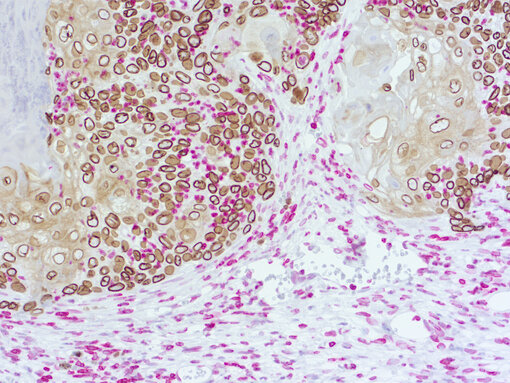

Ki67 is a marker of cell proliferation and an important biomarker for therapy response. Immunohistochemical doublestaining of human and mouse Ki67 is useful to simultaneously quantify proliferation in human and murine cell compartments (Figure 3B).

Immunohistochemical doublestaining of patient-derived pancreas cancer model

Figure 3b: Immunohistochemical doublestaining of patient-derived pancreas cancer model using rabbit anti-human Ki67 (cat.no. HS-398 003; AP-RED, red color) and rat anti-mouse Ki67 (cat.no. HS-398 117; DAB, brown color). Nuclei were counterstained with haematoxylin.